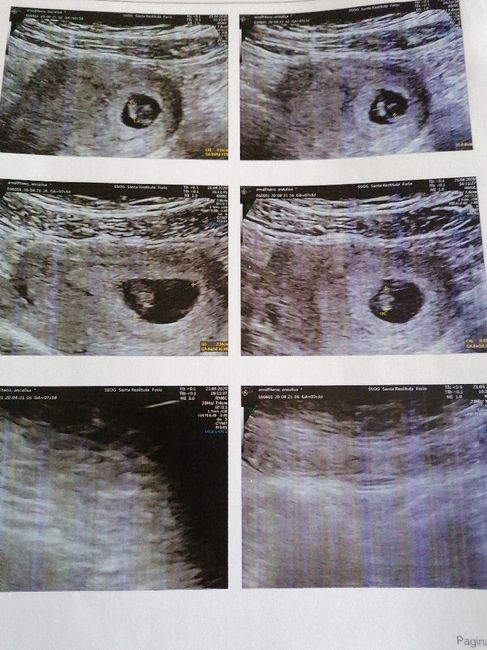

Oggi ho fatto il Gtest e tra dieci giorni circa oltre agli altri esami avrò il risultato anche del sesso, così un po’ per divertirci a sfatare miti volevo allegare 2 ecografie una di 8 settimane fatta internamente e una di 11 (oggi) fatta...